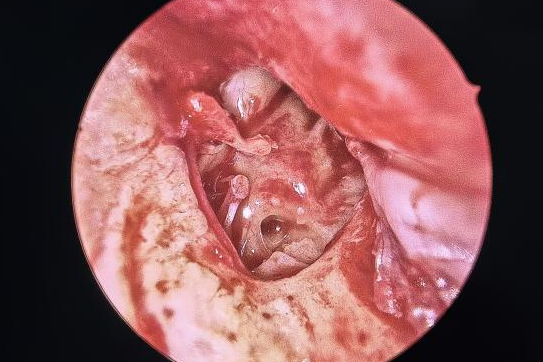

耳朵反复流脓、听力下降还有异味?当心,这可能是慢性化脓性中耳炎的症状。由于早期症状时好时坏,很多人觉得不是大问题,但拖延不治可能对听力造成不可逆的损伤。今天我们就来认清它的真面目,学会如何科学应对。 什么是“慢性化脓性中耳炎”? 慢性化脓性中耳炎,俗称“灌耳心”,典型症状包括耳内反复流脓(常为脓性分泌物,严重时可伴有臭味)、听力下降以及耳鸣等,部分患者还可能伴有眩晕。很多人是从小时候就开始出现症状,尤其是耳朵进水后容易急性发作或加重,成年后,听力持续减退往往成为主要困扰。 如果不及时治疗,炎症可能“向上”蔓延到颅内,引发脑膜炎、脑脓肿等危及生命的严重并发症。也可能侵犯面部神经或平衡器官,导致面瘫、持续眩晕或平衡障碍。最直接的后果是听力会不可逆地下降,严重时可能导致完全失聪。 “慢性化脓性中耳炎” 如何治疗? 慢性化脓性中耳炎的基础治疗需先用双氧水或生理盐水清洗耳道脓液,再滴入敏感抗生素耳液(如氧氟沙星滴耳液)。急性发作或重症时需口服或静脉注射抗生素并辅以抗炎药。若药物控制不佳或已有器质性病变,则需手术,包括乳突切除术清除病变组、鼓膜成形术修复穿孔鼓膜、听骨链重建术改善传音功能及胆脂瘤清除术清除胆脂等。 患者常见问题解答 问 手术后多久能恢复听力? 答 术后恢复情况与手术方式、个人身体情况有关。若为鼓膜修补手术,术后1—3个月左右,听力会逐渐改善,若进行听骨链重建手术,通常需要 3 到 6 个月,听力才能趋于稳定。术后需定期复查,监测听力恢复情况。 问 儿童患者能手术吗? 答 如果孩子的病情确实需要手术,家长不用太担心,儿童也是可以接受手术治疗的。医生会根据孩子的年龄大小、病情严重程度,选择最适合的手术方式,比如现在常用的微创技术,就能尽量减少手术对孩子耳朵的创伤,让孩子恢复的更好。 问 如何预防复发? 答 术后严格遵医嘱用药、复查,避免感冒及耳部进水,保持鼻腔通畅,减少咽鼓管阻塞。 贵州航天医院耳鼻咽喉科简介 张光进 中共党员,耳鼻咽喉科主任,副主任医师 临床擅长:对耳鼻喉头颈常见病的诊治具有丰富的临床经验,擅长鼻内镜、耳内镜、耳显微、头颈咽喉部肿瘤及眩晕手法复位等的诊疗。 曾先后前往第三军医大学西南医院、复旦大学耳鼻喉科医院、上海新华医院及北京友谊医院进修学习;遵义市医学会常务委员;主持及参与级科研课题2项,发表专业论文10余篇。 陈维信 九三学社社员,耳鼻咽喉科主任医师 临床擅长:对耳鼻咽喉科常见疾病的诊治具有丰富的临床经验,擅长耳、鼻、喉及头颈部位的手术。 曾先后前往上海交通大学附属仁济医院耳鼻喉-头颈外科、北京大学人民医院耳鼻喉-头颈外科参加鼻内镜外科进修学习。中国睡眠研究会委员,贵州省医学会耳鼻喉-头颈外科学分会委员,贵州省耳鼻喉-头颈外科学会理事,贵州省医学会变态反应学分会委员,贵州省防聋治聋技术指导组专家,遵义市耳鼻喉科分会副主任委员,遵义市医疗事故鉴定专家库成员;主持省部级科研课题2项,发表专业论文20余篇。 秦 晋 耳鼻咽喉科副主任医师 临床擅长:对耳鼻咽喉科常见疾病的诊治具有丰富的临床经验,擅长耳、鼻、喉及头颈部位的手术。 遵义市医学会常务委员;曾先后在第三军医大学西南医院、湖南湘雅鼻颅底培训班进修学习。 贵州航天医院耳鼻咽喉科简介 基本情况 贵州航天医院耳鼻咽喉科拥有一支经验丰富、技术精湛的医疗团队,共有医师9名,其中副高级以上专家5名,医学硕士2名,开放床位20张,拥有德国WOLF鼻窦内窥镜系统、日本奥林巴斯电子喉镜、奥林巴斯电子鼻咽镜、丹麦临床听力监测设备、声导抗仪、听觉诱发电位、耳声发射仪、美国杰西低温等离子治疗仪、杭州好克鼻窦内窥镜系统、鼻动力系统、耳显微镜、耳用电钻、微波治疗仪等设备。 专科特色 (一)耳部疾病 耳内镜下胆脂瘤切除术、III型鼓室成形术+人工听骨链重建术。 (二)鼻部疾病 内镜下鼻息肉切除术、鼻窦功能开放术。 (三)咽喉疾病 内镜下扁桃体、腺样体低温等离子切除术 (四)交叉学科 1.经鼻内镜下眶内肿瘤切除术 2.经鼻内镜下鼻腔泪囊吻合术 诊疗范围 (一)常见耳疾的诊断和治疗:中耳炎、耳聋、耳鸣等。通过各种耳科检查手段,如耳镜检查、听力测试和耳脑干听觉诱发电位检查等,准确诊断患者病情,制定个性化治疗方案。 (二)鼻炎、鼻窦炎、鼻出血等鼻科疾病的诊断和治疗:采用微创技术,如鼻内窥镜检查、低温等离子手术等,为患者提供有效的治疗方案。 (三)喉炎、声带息肉、声带白斑等喉科疾病的诊断和治疗:通过声带电子镜、喉镜等设备,准确判断患者的喉部病变,为患者提供精准的治疗方案。 (四)鼻眼、鼻颅底相关手术。